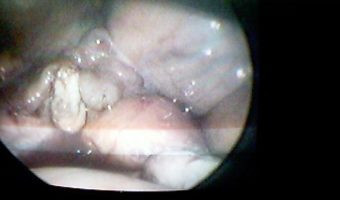

Dr. Leonel Edgardo Martínez Villacorta

Absceso Gigante de Riñón

Medicos Cirujanos > Laparoscopistas

VER GALERÍA